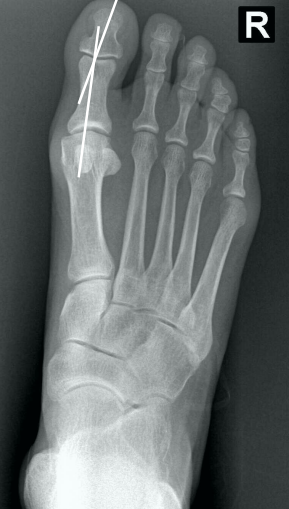

• Como verificar na radiografia AP com carga, se há luxação do sesamóide e classifica-lo de acordo com Mann e Coughlin?

• Traça-se um linha no eixo do 1° mtt e verifica o quanto, em “%”, a linha toca o sesamóide tibial (medial)